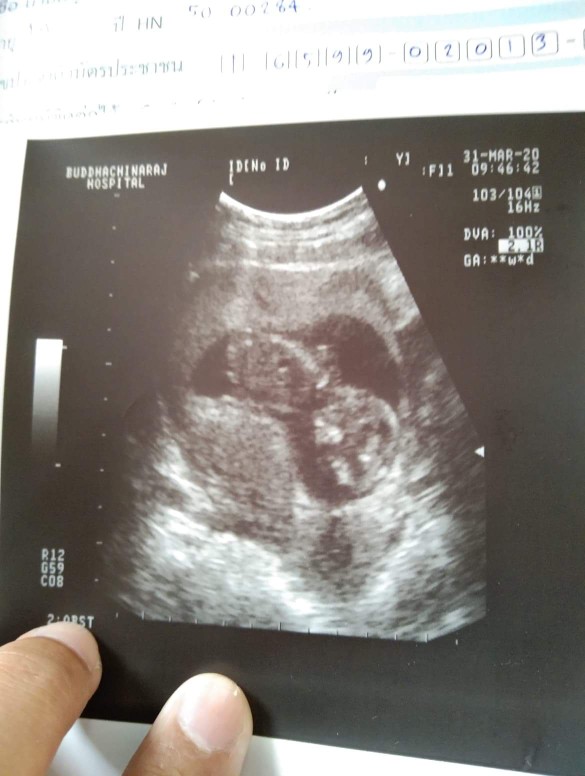

11 สัปดาห์

11 สัปดาห์ ซาวด์มาเจอลูกแบบนี้ถือว่าเขาตัวใหญ่ไหมคะหรือปกติ

11 สัปดาห์ค่ะ